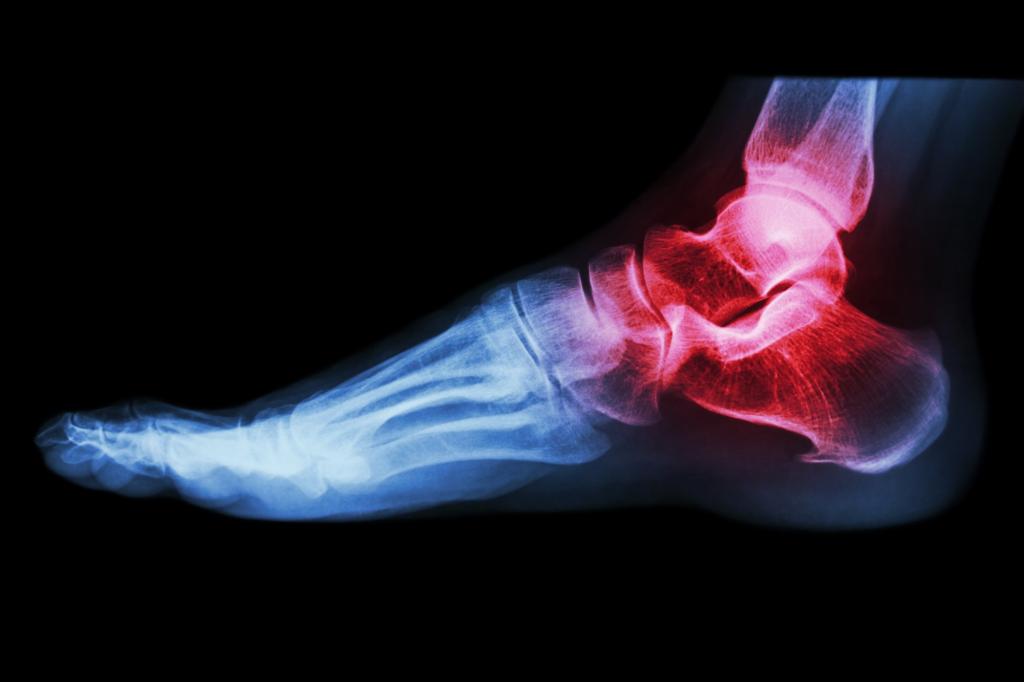

Диагностика недуга подразумевает проведение следующих исследований:

- Рентгенографии. Назначается во всех случаях. Рентгенография — это главный метод диагностики, на основании результатов которого врач сможет составить максимально действенную схему лечения растяжения связок голеностопного сустава. Исследование выполняется как в боковой, так и в прямой проекции.

- УЗИ. Данное исследование является дополнительным. Врач назначает его в том случае, если нужно узнать, имеет ли место быть разрыв волокон одной связки или даже целого пучка.

В тяжелых случаях показано проведение МРТ. С помощью данного исследования врач получает возможность оценить целесообразность проведения хирургического вмешательства и составить план операции.